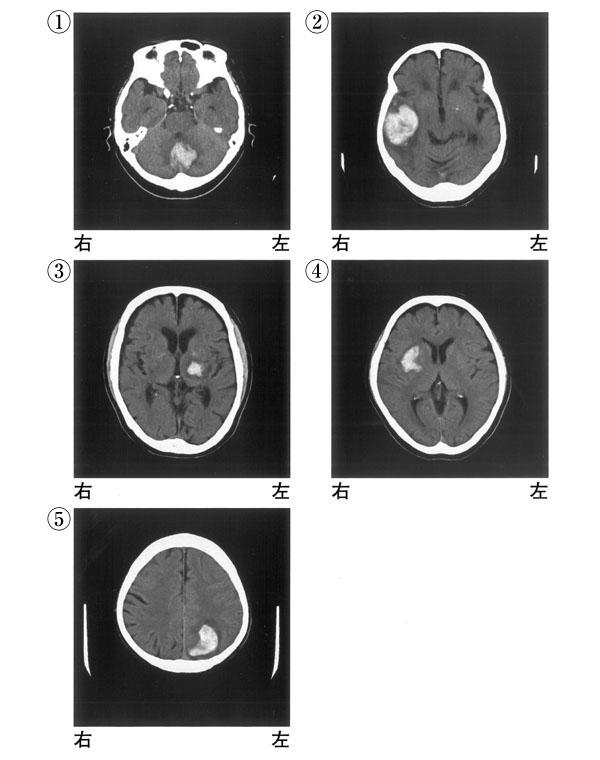

65歳の男性。右利き。突然の意識障害で搬送された。くも膜下出血の診断で、破裂脳動脈瘤のクリッピング手術を施行された。発症後3か月の頭部CTを示す。この患者に出現しやすい症状はどれか。

上着の左右を間違えて袖を通す。

ジェスチャーの模倣ができない。

移動する時に左側の人や物にぶつかりやすい。

知っている人なのに声を聞かないとわからない。

担当理学療法士に毎日初対面のように挨拶する。

CT(①~⑤)を別に示す。片麻痺を呈する可能性が高いのはどれか。2つ選べ。

①

②

③

④

⑤